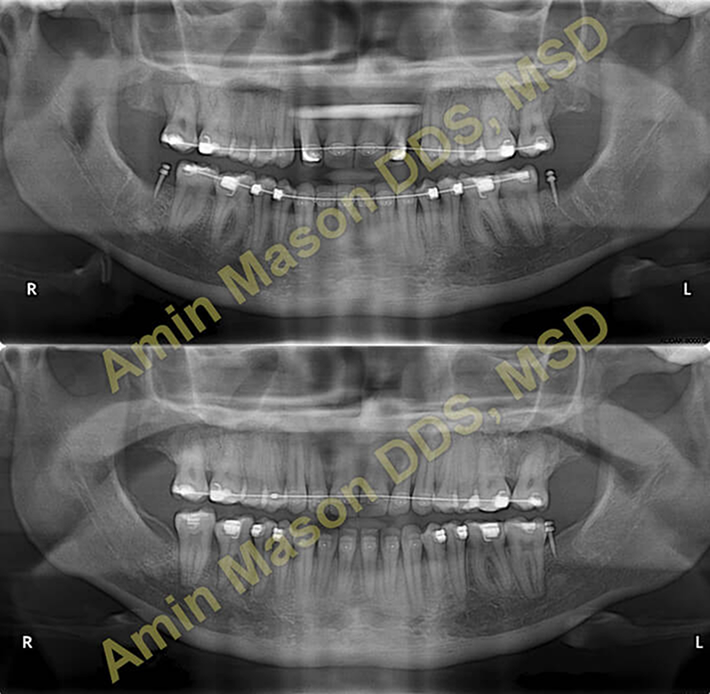

Class III / Underbite Correction Case

Adult patient with severe underbite and skeletal class III, patient was treated non-surgically using multiple TADS.

Molar Protraction Case

Adult patient with missing mandibular first molars. TADS were used to protract (pull forward) the 2nd and 3rd molars (wisdom teeth). Patient was saved from getting implants for the missing teeth.